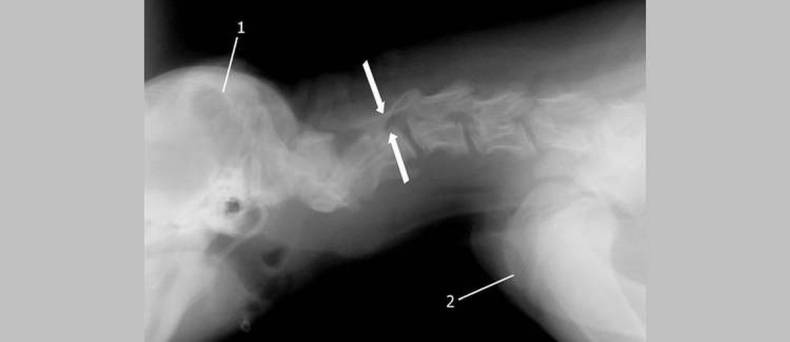

De diagnose van HNP kan worden gesteld door middel van röntgenfoto's of een MRI-scan. Behandeling kan bestaan uit pijnstillers, ontstekingsremmende medicijnen, fysiotherapie en soms chirurgie. Het doel van de behandeling is om de pijn te verminderen en de mobiliteit te verbeteren.